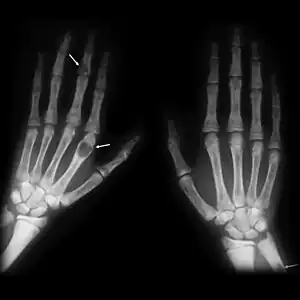

| Brown tumours of the hands in a patient with hyperparathyroidism. |